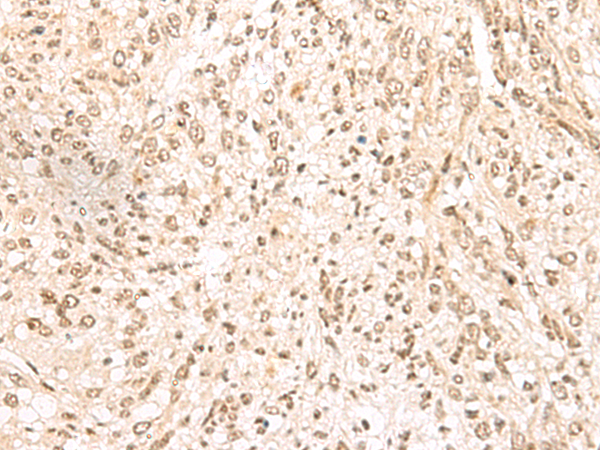

分类: 科研抗体货号: P09891别名: Txl; TXNL; TRP32; TXL-1; HEL-S-114应用: WB,IHC反应种属: Human, Mouse, Rat